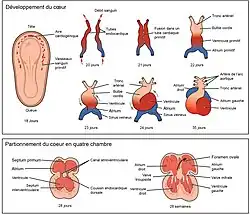

Embryologie

Le cœur est le premier organe fonctionnel à se développer et commence à battre et à pomper le sang environ trois semaines après le début de l'embryogenèse. Ce démarrage précoce est crucial pour le développement embryonnaire et prénatal ultérieur.

Le cœur dérive du mésenchyme splanchnopleurique de la plaque neurale qui forme la région cardiogénique. Deux tubes endocardiques se forment ici et fusionnent pour former un tube cardiaque primitif connu sous le nom de cœur tubulaire[6]. Entre la troisième et la quatrième semaine, le tube cardiaque s'allonge et commence à se plier pour former une forme en S dans le péricarde. Cela place les chambres et les principaux vaisseaux dans le bon alignement pour le cœur développé. Le développement ultérieur comprendra la formation des septa et des valvules ainsi que le remodelage des cavités cardiaques. À la fin de la cinquième semaine, les septa sont terminés et à la neuvième semaine, les valvules cardiaques sont terminées[7].

Avant la cinquième semaine, il y a une ouverture dans le cœur fœtal appelée foramen ovale. Le foramen ovale permettait au sang du cœur fœtal de passer directement de l'oreillette droite à l'oreillette gauche, permettant ainsi à une partie du sang de contourner les poumons. Quelques secondes après la naissance, un lambeau de tissu appelé septum primum, qui servait auparavant de valvule, ferme le foramen ovale et établit le schéma typique de circulation cardiaque. Une dépression à la surface de l'oreillette droite subsiste à l'endroit où se trouvait le foramen ovale, appelée fosse ovale[7].

Le cœur embryonnaire commence à battre environ 22 jours après la conception (5 semaines après les dernières règles menstruelles normales, LMP). Il commence à battre à une fréquence proche de celle de la mère, soit environ 75 à 80 battements par minute (bpm). La fréquence cardiaque embryonnaire s'accélère alors et atteint un pic de 165 à 185 bpm au début de la 7e semaine[8]. Après 9 semaines (début du stade fœtal), elle commence à décélérer, ralentissant jusqu'à environ 145 (± 25) bpm à la naissance. Il n'y a aucune différence entre les fréquences cardiaques des femmes et des hommes avant la naissance[7].